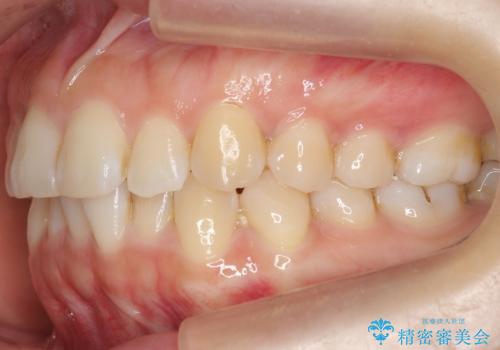

下の前歯のがたつき インビザラインで

- 前歯のがたつきを主訴に来院。

インビザラインで上下の前歯をわずかに削って並べました。

下の歯の叢生を並べると多少ブラックトライアングルがでることがあります。